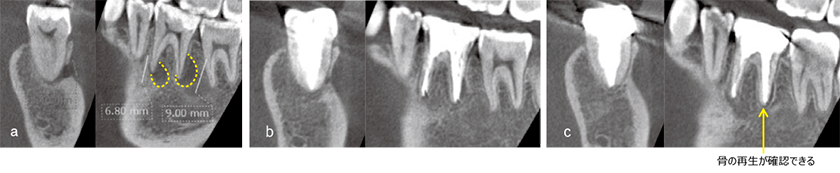

An X-ray transmission image with a width diameter of approximately 26.5 mm was observed in the white tooth area on the right side of the mandible, and root canal treatment had been performed on 6┐. The electro pulp examination revealed that 7┐ and 5┐ did not show any signs of living reaction, so root canal treatment was performed on the three teeth according to the usual method. After removing the contaminated contents and dentin from the root canal, passive ultrasonic irrigation was performed using 2% sodium hypochlorite. The patient underwent passive ultrasonic irrigation using 2% sodium hypochlorite, and calcium hydroxide was applied three times, but there was no significant change in the findings in the root canal. Therefore, the 6┐ proximal root tip equivalent was dissected with a 5×5 mm full-layer valve, the buccal bone was perforated by approximately 3-4 mm, and EMAT was performed through the 65┐ root canal after a possible curettage of the cyst wall with the aim of promoting bone formation. After 3 months, osteogenesis was already seen in the bone wall of the lesion, and after 2 years and 1 month, the bone trabecular structure was almost equal to that of the surrounding bone.

Although it is often reported that the size of the lesion affects the success rate of treatment, we believe that the fact that the bone defect improved in 3 months may be due to the healing-promoting effect of EMAT, even though curettage of the cyst wall was also used in this case.